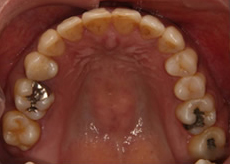

治療後はきれいに整っています。

左上下顎臼歯部に著しい叢生があり、下顎臼歯部が大きく舌側へ傾斜していました。左はもちろん、右側も歯並びが崩れていて、右ではほとんど咬んでいなかったそうです。